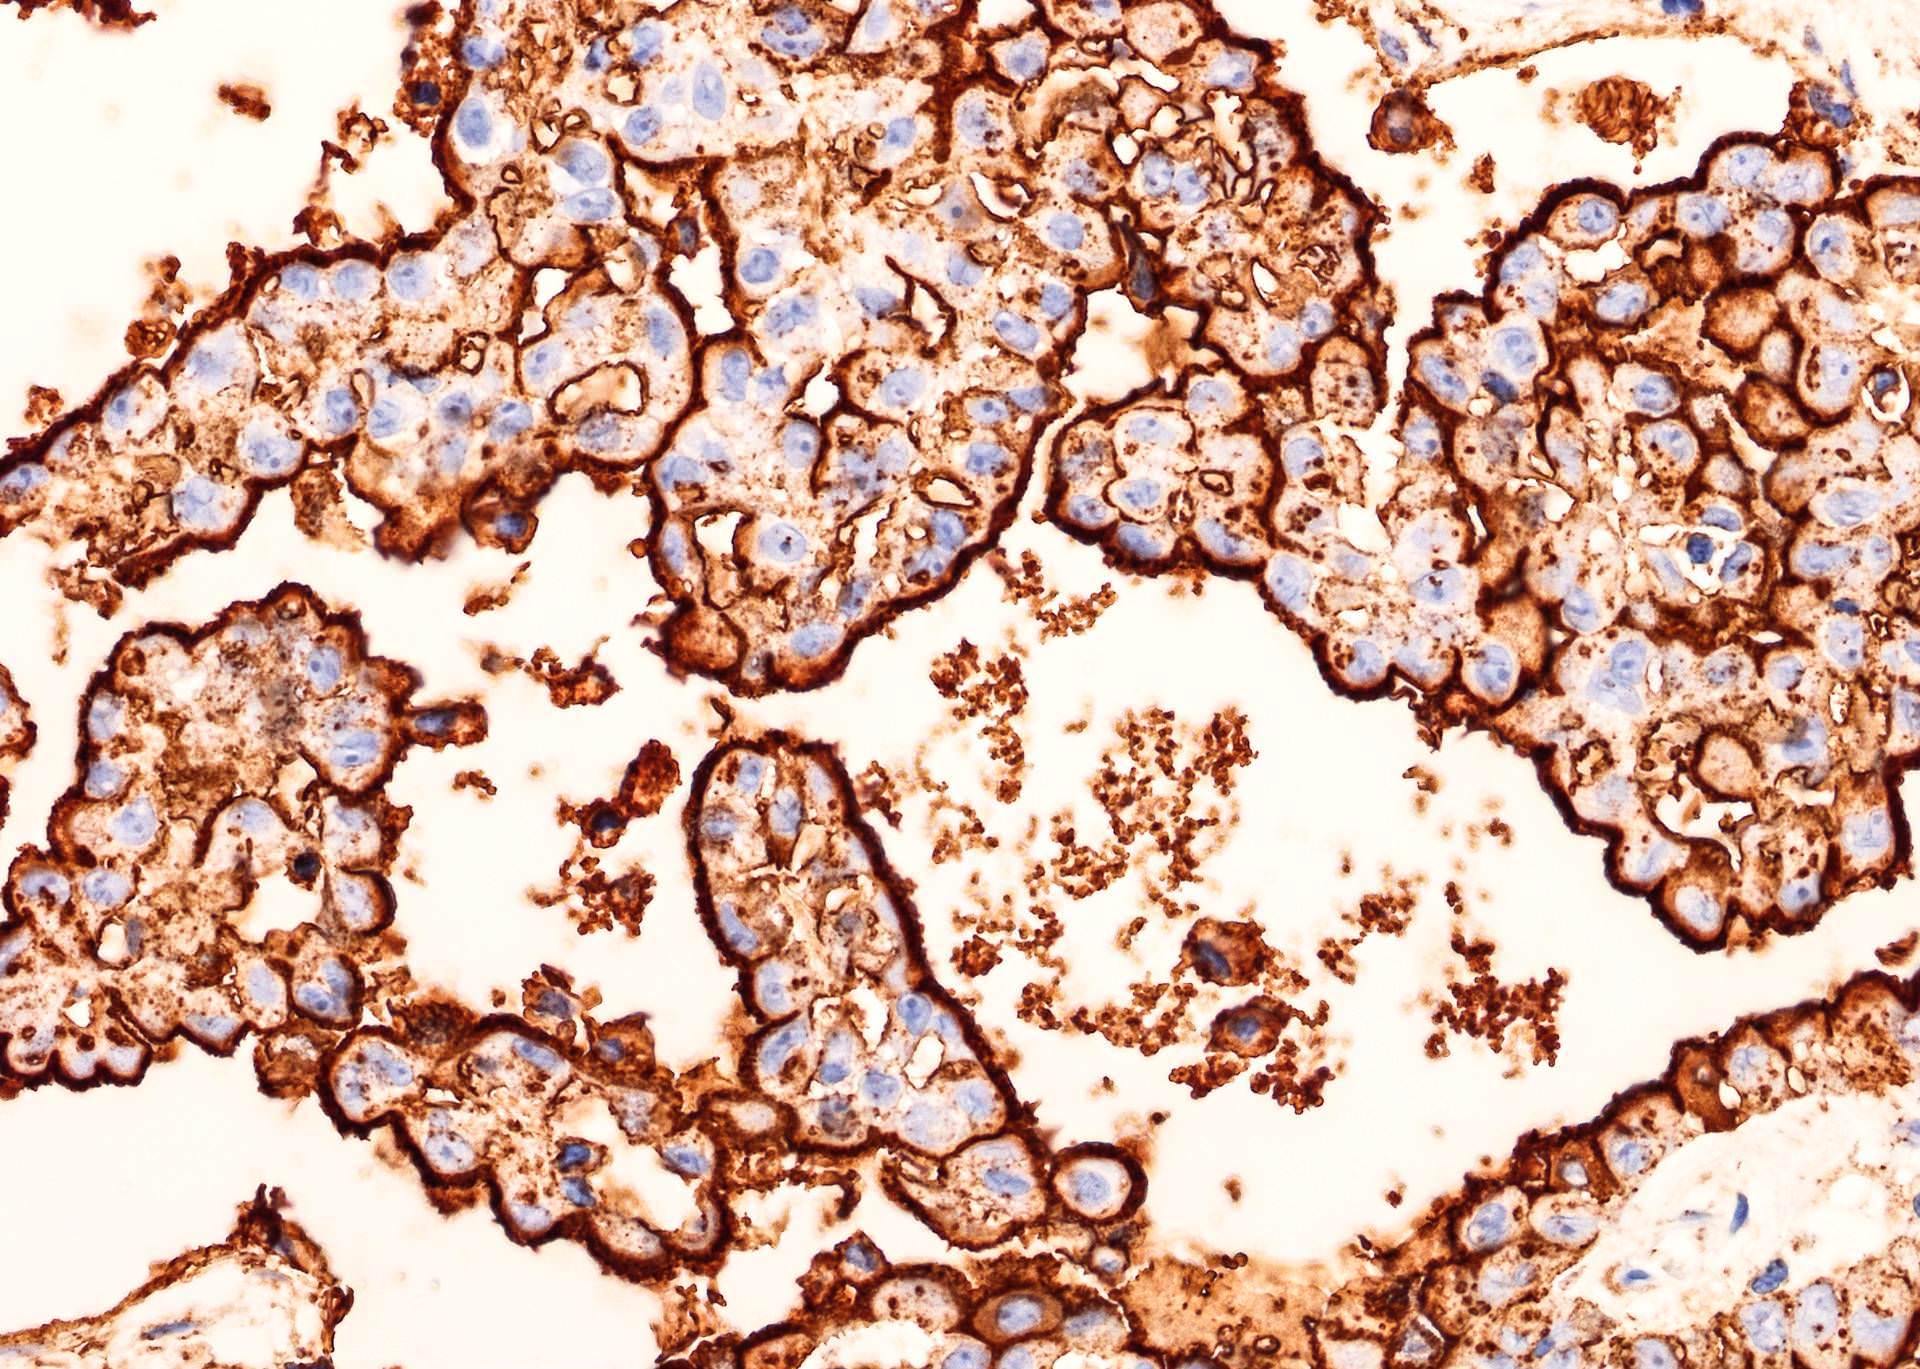

Striking membranous staining

Strong membranous HBME-1 immunoreactivity

Strong HBME-1

immunoreactivity

with apical membrane

accentuation